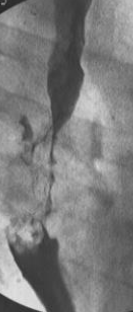

Neoplasm esofagian malign infiltrativ